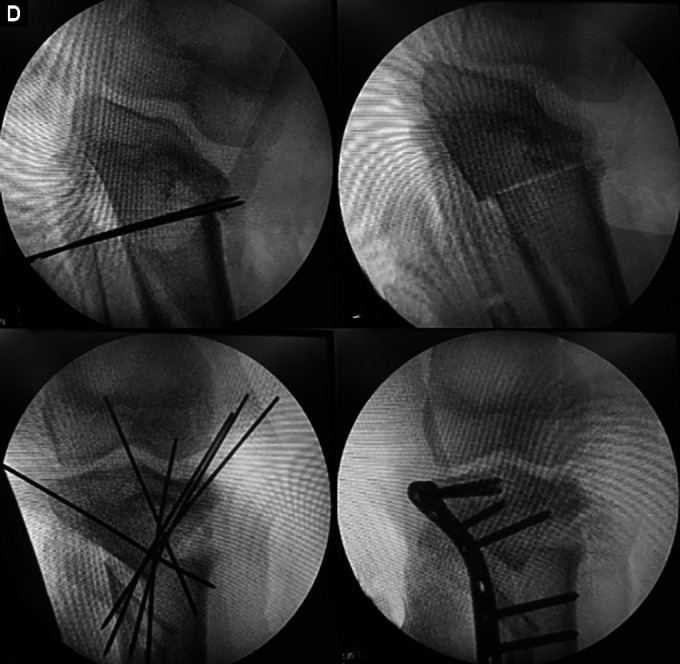

Background: Tibia vara is a three-dimensional deformity of the proximal tibia, varus, internal tibial torsion and procurvatum. It is an uncommon deformity with the surgical management varied. This study describes the outcomes of tibia vara management using a corrective transverse osteotomy in one centre.

Materials and methods: A retrospective cohort study was conducted involving eight patients with tibia vara (ten tibias). Consent was obtained for treatment using an acute corrective osteotomy. Measurements of Drennan's angle, the tibiofemoral angle (TFA) and the procurvatum angle were measured preoperatively and postoperatively both just after surgery and at 1 year. A validated questionnaire-the Knee Outcome Survey of Activity Daily Living (KOS-ADL)-was utilised to assess clinical function and outcome. Also recorded were the intraoperative and postoperative complications, the radiological lower limb alignments, the union rate and the recurrence of deformity.

Results: There were eight patients involved in this study with a total of ten tibias (six with unilateral tibias and two with bilateral tibias). The mean age of the patients was 11.3 years old (ranging from 8 to 15 years old) with most males (five males and three females). The affected tibias were 6 right sided and 4 left sided. Measurements of Drennan's angle, the TFA and the procurvatum angle were used to determine lower limb alignment preoperatively, postoperatively (immediate post-surgery) and at 1-year follow-up. Functional parameters were measured using the KOS-ADL. A descriptive analysis between the preoperative and postoperative variables was done. The mean for Drennan's angle was 21.6 (±5.2) preoperatively, 3.6 (± 2.3) postoperatively and 4.9 (±2.8) at 1-year follow-up. The TFA was improved from 22.6 (±6.1) preoperatively to 3.5 (±2.8) postoperatively and 4.4 (±2.0) at 1-year follow-up. The procurvatum angle was improved preoperatively from 8.20 (±7.5) to 2.40 (±2.5) postoperatively and 2.20 (±2.5) at 1-year follow-up. At the latest follow-up, the ADLS mean score was 98.5 (±2.6) while the SAS mean score was 97.5 (±3.3). The mean length follow-up period was 2 years (ranging from 1 year to 3 years). None of the patients developed postoperative complications with all achieving union without deformity recurrence in the period of observation.

Conclusion: This study revealed that acute correction via a corrective transverse osteotomy of the tibia is a safe and effective method in treating tibia vara.